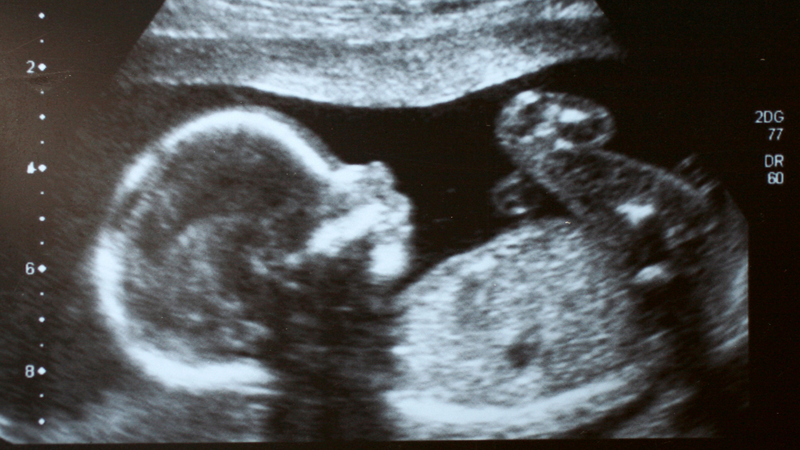

Ngay từ khi biết tin mang thai, nhiều mẹ đã bắt đầu suy đoán xem bé là “công chúa” hay “hoàng tử”. Dù việc xác định giới tính thai nhi chính xác cần đến siêu âm hoặc xét nghiệm, nhưng những quan sát từ cảm giác trong thai kỳ vẫn thường được chia sẻ như một “bí kíp dân gian”. Vậy sự khác nhau giữa mang thai con trai và con gái có gì thú vị? Hãy cùng khám phá qua các phần dưới đây.

Các dấu hiệu kể trên chủ yếu mang tính tham khảo, chưa thể dùng làm cơ sở để xác định giới tính thai nhi. Việc chẩn đoán chính xác vẫn cần đến các phương pháp y học như siêu âm đúng thời điểm hoặc xét nghiệm phân tích ADN trong thai kỳ.

Nếu bạn muốn biết giới tính thai nhi một cách chính xác hơn, có thể tham khảo các phương pháp y khoa sau:

Tổ chức ACOG khuyến nghị xét nghiệm NIPT không chỉ để biết giới tính mà còn giúp sàng lọc các bất thường nhiễm sắc thể như hội chứng Down, Edwards…